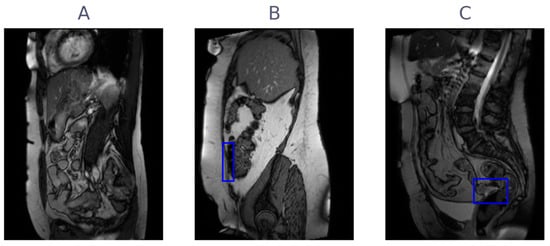

The flow of patients in the study is shown in Figure 1. Of the 10 patients included in the observer study, 9 were female. The age of the patients ranged from 30 to 74, with a mean age of 54. Of the seven patients with adhesions indicated in the original radiology report, six patients had adhesions in the lesser pelvis, 2 patients had adhesions between bowel loops, and none had adhesions to the anterior abdominal wall. All scans were acquired in 2019 and were reviewed by 15 observers between March 2020 and October 2020, with 3 observers forming the consensus group. The consensus meeting resulted in a unanimous reference standard, where 7 of 10 patients had adhesions (3 negative), and 19 of 61 slices had adhesions (42 negative). Figure 2 shows three examples of cine-MRI slices, with the consensus annotations shown as blue boxes. Since cine-MRI is a dynamic modality, these examples are best viewed as movies. They are included in the Supplementary Files (Videos S1–S3). A subset of five observers, containing two observers from the consensus group, reviewed the scans a second time between May 2021 and June 2021. The years of general experience, including residency, ranged from 0 to 30, with a mean of 7. The amount of cine-MRI cases reviewed ranged from 0 to 300, with a mean of 52. The amount of adhesion cine-MRI cases reviewed ranged from 0 to 300, with a mean of 32. A detailed overview of the observer experience, group assignment, and clinical significance thresholds is provided in Table 1.

Figure 2.

Three examples of cine-MRI slice with typical adhesions, with consensus annotations overlayed as blue boxes. (A) A slice without adhesions present, (B) a slice with an adhesion to the anterior abdominal wall, and (C) a slice with an adhesion in the pelvic area.